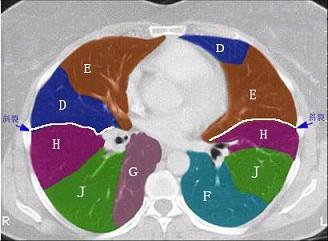

结合肺段模式心室层面(如图),选出右肺上叶的组成 ( )A.AB.A+BC.A+B+CD.A+B+C+DE.A+B+C+D+E

问题 结合肺段模式心室层面(如图),选出右肺上叶的组成 ( )

选项 A.A B.A+B C.A+B+C D.A+B+C+D E.A+B+C+D+E

答案 C